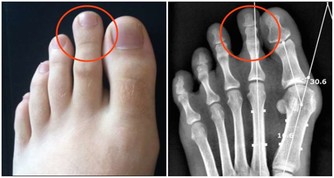

過於敏感或者皮膚瘙癢是肝硬化的症狀,肝臟疾病在肝臟瘢痕組織形成,血液中膽汁酸的積累會加重你的皮膚敏感和發癢。中醫認為指甲依賴於肝血和肝氣的榮養,肝血虛時指甲上容易長豎紋、凹陷,肝臟排毒不暢時,也會長。這一小細節也許大家都不在意,但是確實肝臟在向你發出最大的信號。